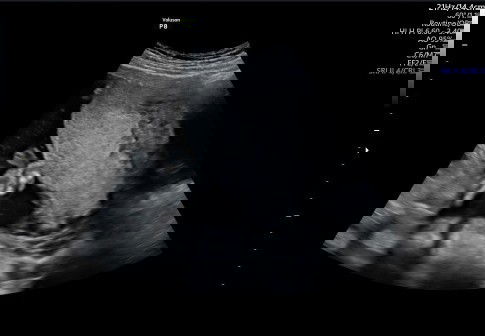

Assalamualaikum.... Hbis USG usia 29 mggu. Tp posisi bayi sungsang. Dan ari2 hmpir menutup jaln lahir (plasenta previa). Satu buln yg lalu USG jg sma plasenta previa. Udah sujud2. Udah senam hamil tp dlm sebuln tidak ada perubahan. Yg mau saya tanyakan ap kah masih mungkin lahiran normal??? Ap kah bayi masih bisa pindah posisi dan plasenta jg bergeser??? Selain senam hamil dan sujud2.usaha ap lg yg hrus d lakukan?? Trimakasih yg udah mau jawab.....#seriusnanya #bantusharing .